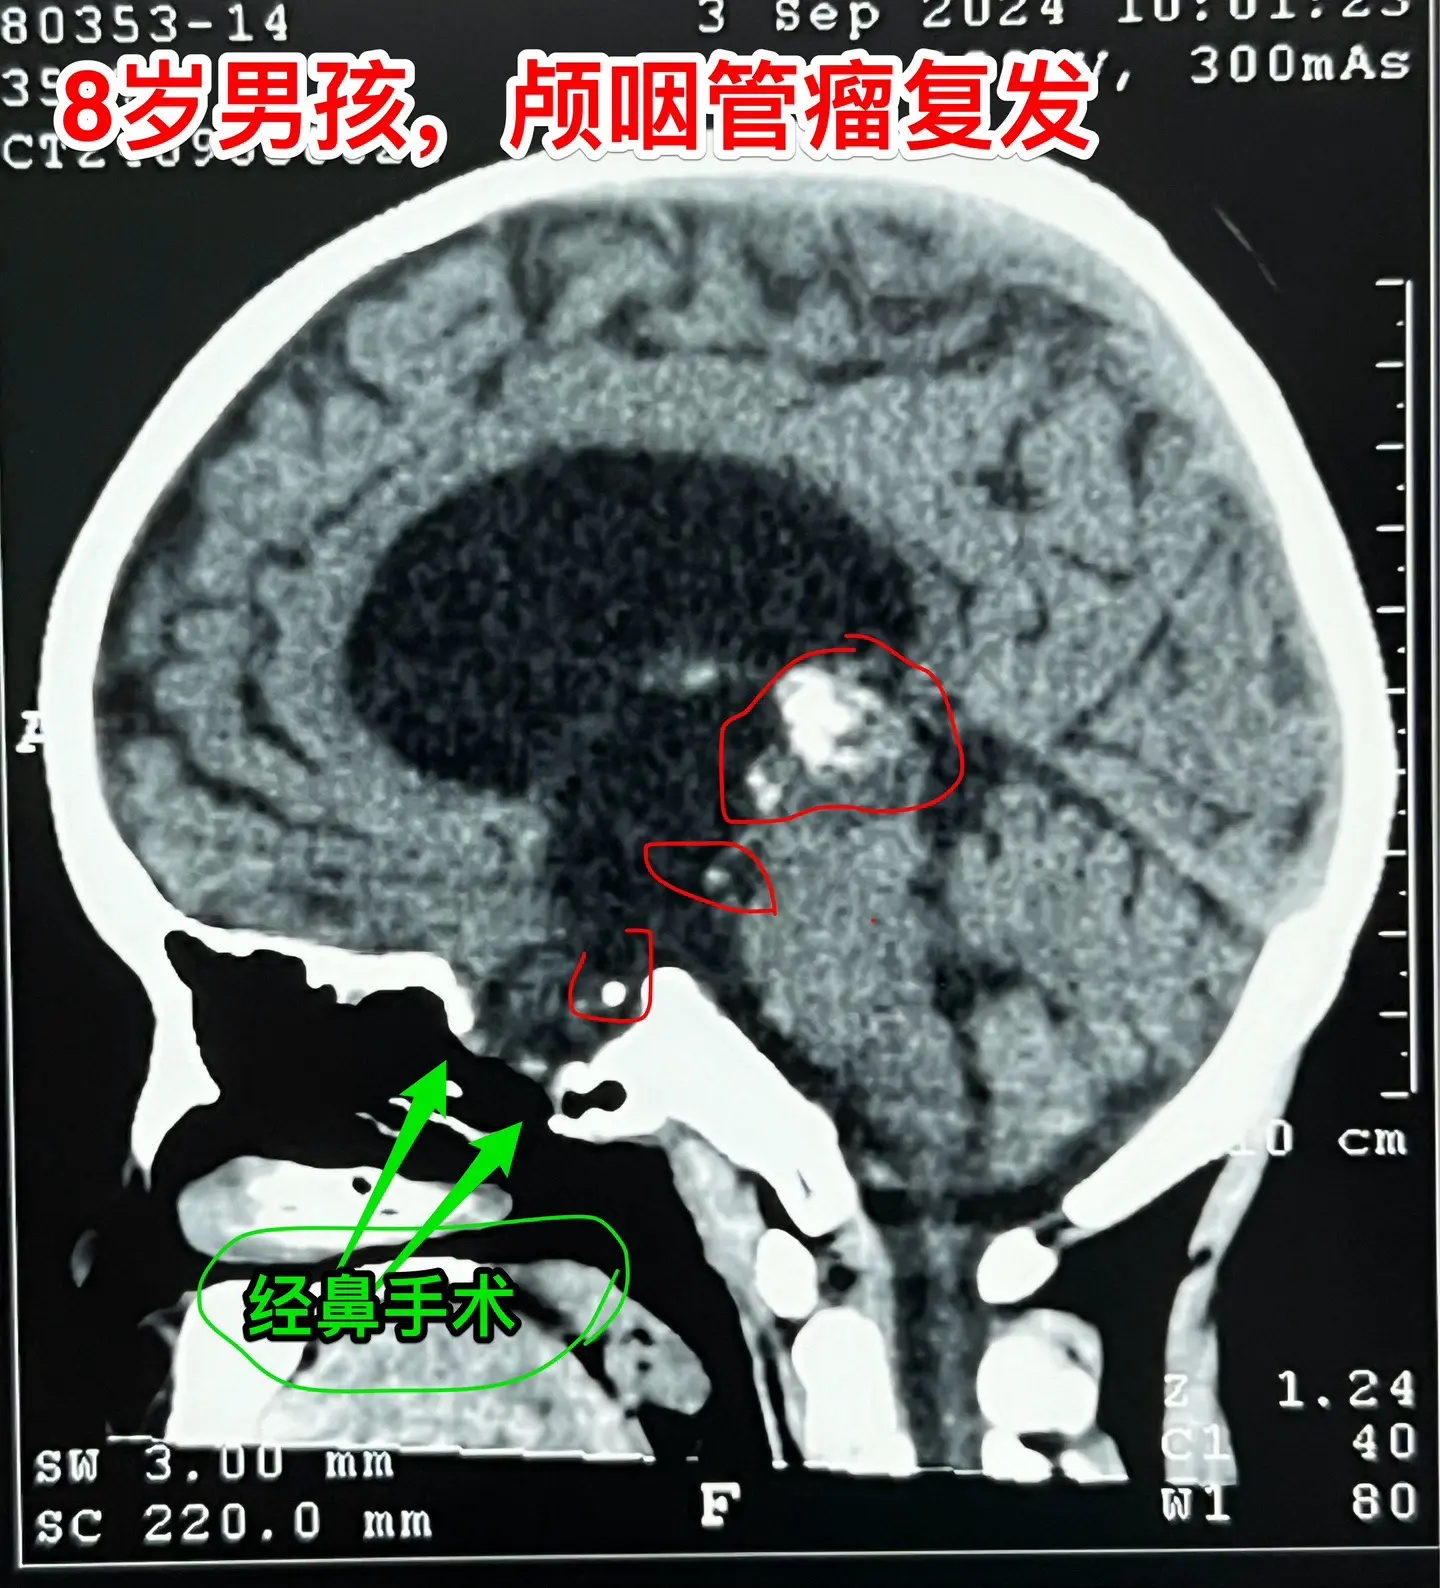

昆明男孩在14个月时间内两次大手术。昆明的8岁男孩子,2023.3在昆明发现颅咽管瘤,体积很大。这样的肿瘤想切干净是很有难度的。2023.7.1在北京市某医院作了经鼻手术,当时告知家长肿瘤得到完全切除。 2024.7复查磁共振显示第三脑室后部肿瘤复发,当时小孩子没有任何症状,找我咨询,我建议先观察。2024.9小孩子出现视物模糊、眼球活动障碍,复查磁共振显示第三脑室后部的肿瘤体积增大了,不得不接受手术治疗。住院后作CT发现肿瘤不单单是在第三脑室后部,鞍区及鞍上均发现散在的钙化。这就提示残留的肿瘤远不止一处。 9.25作了开颅手术,顺利切除所能看见的十来个肿瘤灶。手术后CT显示鞍区及鞍上的小钙化均被切除。我如实告诉家长,后面还不保险,肿瘤仍有复发的可能性,需要定期复查。